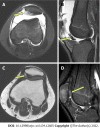

Case summary: A 15-year-old male with a large patellar cartilage defect due to patellar dislocation was treated via human umbilical cord blood-derived mesenchymal stem cell (hUCB-MSC) implantation. To our knowledge, this is the first report of this treatment for this purpose. The patient recovered well as indicated by good visual analog scale, International Knee Documentation Committee and McMaster Universities Osteoarthritis Index scores. Magnetic resonance imaging showed cartilage regeneration 18 mo postoperatively.